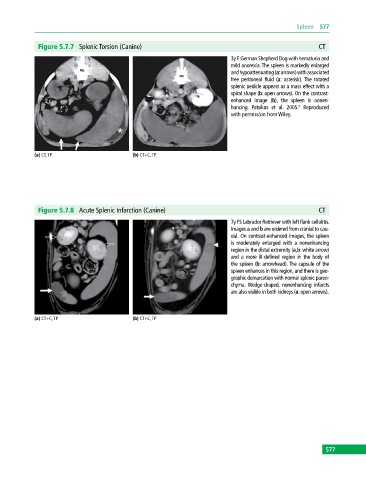

Figure 5.7.7 Splenic Torsion (Canine) CT

3y F German Shepherd Dog with hematuria and

mild anorexia. The spleen is markedly enlarged

and hypoattenuating (a: arrows) with associated

free peritoneal fluid (a: asterisk). The rotated

splenic pedicle appears as a mass effect with a

spiral shape (b: open arrows). On the contrast‐

enhanced image (b), the spleen is nonen

hancing. Patsikas et al. 2005. Reproduced

with permission from Wiley.

(a) CT, TP (b) CT+C, TP

Figure 5.7.8 Acute Splenic Infarction (Canine) CT

7y FS Labrador Retriever with left flank cellulitis.

Images a and b are ordered from cranial to cau

dal. On contrast‐enhanced images, the spleen

is moderately enlarged with a nonenhancing

region in the distal extremity (a,b: white arrow)

and a more ill‐defined region in the body of

the spleen (b: arrowhead). The capsule of the

spleen enhances in this region, and there is geo

graphic demarcation with normal splenic paren

chyma. Wedge‐shaped, nonenhancing infarcts

are also visible in both kidneys (a: open arrows).

(a) CT+C, TP (b) CT+C, TP